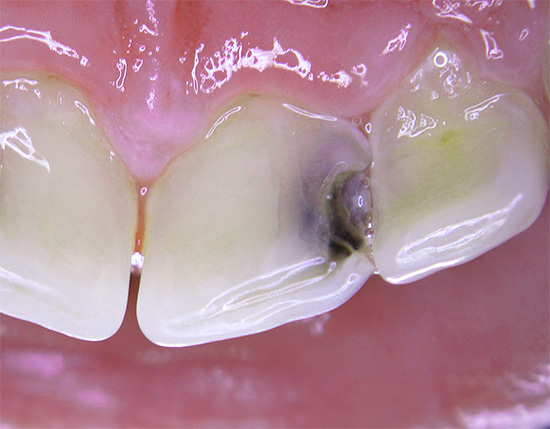

Foto di un dente con una profonda cavità cariata, che ha portato allo sviluppo della pulpite:

Foto di carie profonde sul dente anteriore: